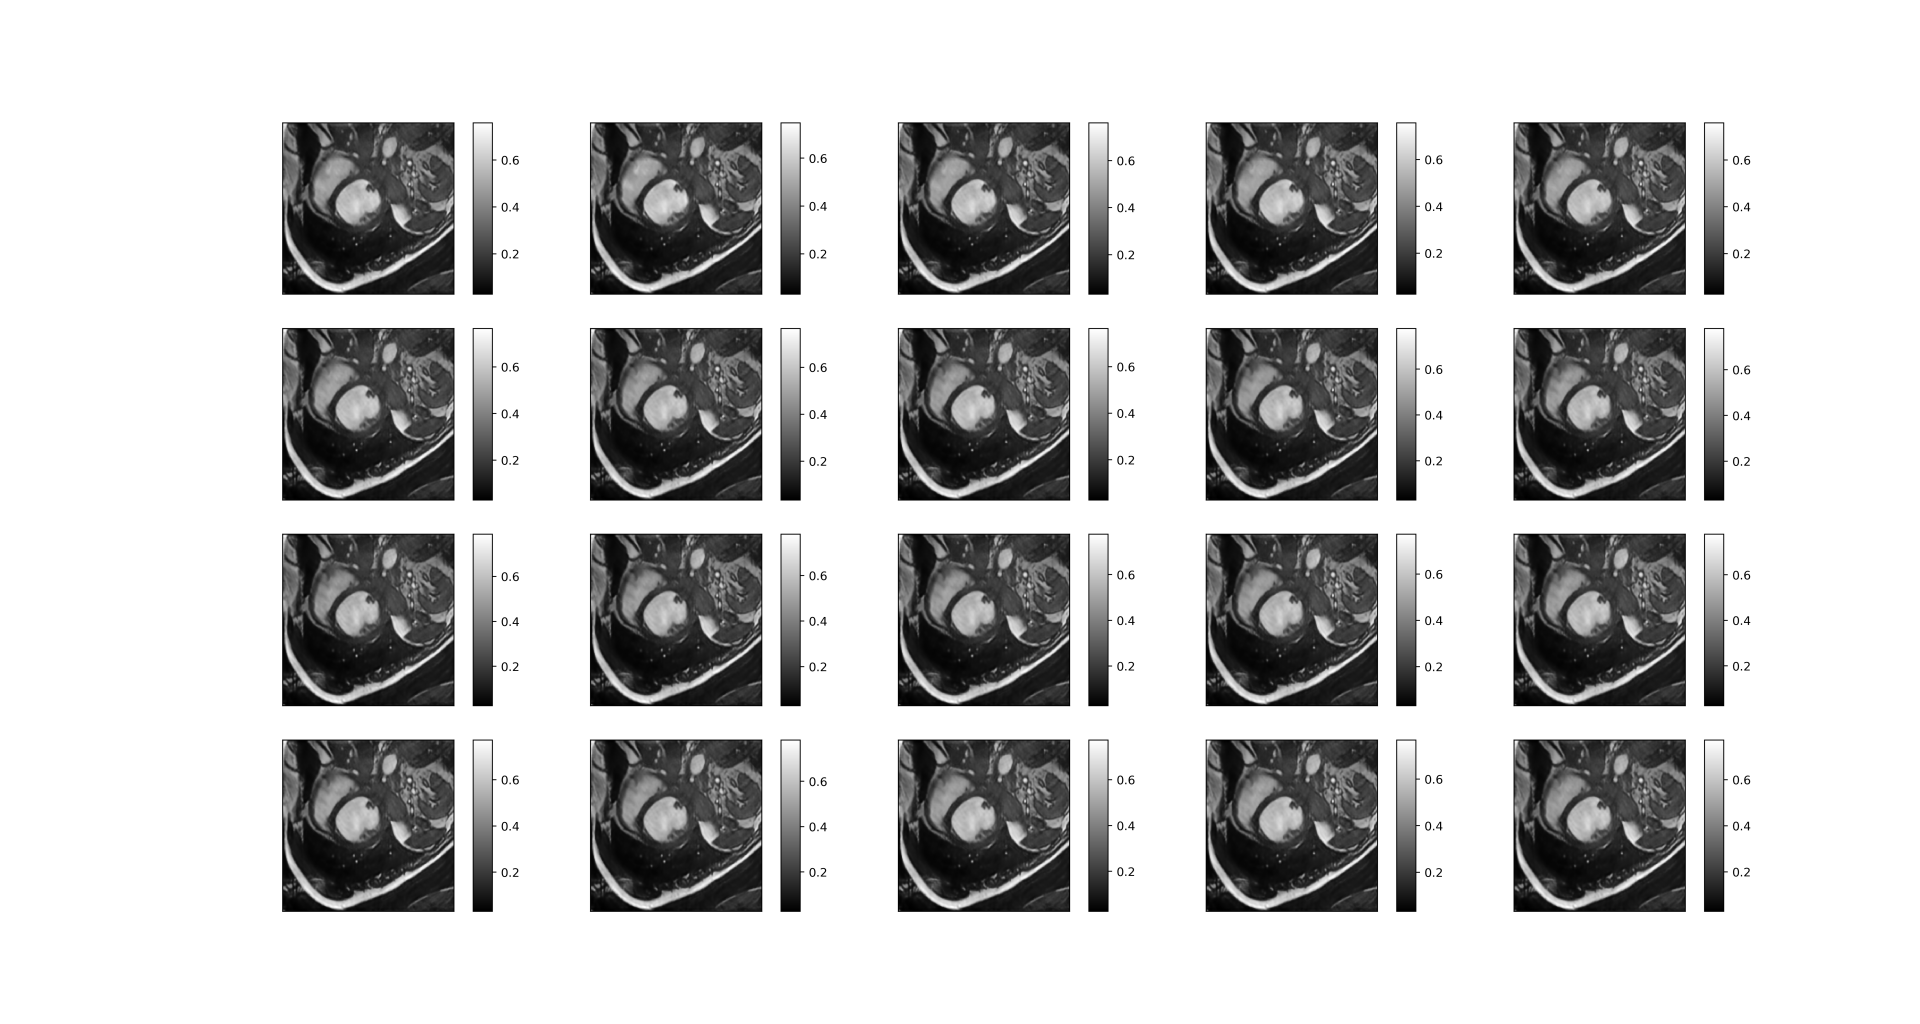

The aliased images(Graph 1.2) and fully sampled images (Graph 1.3) are as follows.

| Graph 1.3 fully sampled image |

A good reconstructed dynamic image is as follows:

| After reconstruction |

|

We can see that the reconstructed image is very clear with many details, though the upper right corner of the picture is slightly blurry.